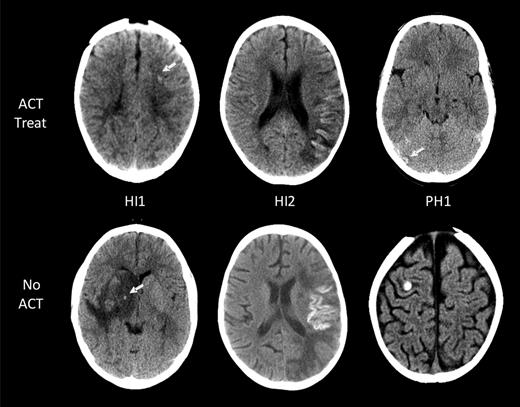

Radiologic data included number and location of infarcts (vascular territory, brain structures, and laterality) and presence of ICH, including hemorrhagic conversion of infarcts at AIS diagnosis and during ACT. For every child with ACT-associated ICH, all brain imaging studies were re-evaluated by the study pediatric neuroradiologist (S.L.) and a pediatric neurologist (A.K. or G.d.V.) blinded to patient clinical data including ACT. ICH scoring was classified according to the European Cooperative Acute Stroke Study (ECASS) definitions: H0, no hemorrhage detected; HI1, hemorrhagic infarct 1: small petechiae, < 50% of infarct area (includes laminar necrosis); HI2, hemorrhagic infarct 2: confluent petechiae, > 50% of infarct area; PH1, parenchymal hemorrhage 1: blood ≤ 30% of infarct area, no or slight space effect; and PH2, parenchymal hemorrhage 2: blood ≥ 30% of infarct area, substantial space effect.18 Changes in ECASS scores over time were documented.

Eleven of the 14 children with ICH had images available for reanalysis and ECASS grading of ICH severity (Table 2).18 The ACT-associated ICH grades in the 7 asymptomatic patients were as follows: HI1 (no cortical laminar necrosis) in 3 patients, HI2 in 3, and PH2 in 1 (Figure 2). All 4 symptomatic ICH patients had HI1 (including cortical laminar necrosis) bleed severity. Among them, 1 patient had evidence of laminar necrosis only, 2 patients had evidence of both laminar necrosis and petechial hemorrhage, and the fourth patient had petechial hemorrhage.

ICH in children with AIS. Intracranial hemorrhages are classified according to the ECASS grading system. Representative examples of the 3 grades encountered (HI1, HI2, and PH1) are shown for both children on ACT (top row) and those not on ACT (bottom row). No larger hematomas or ECASS PH2 were observed in the ACT-treated group. White arrows point at areas of ICH.